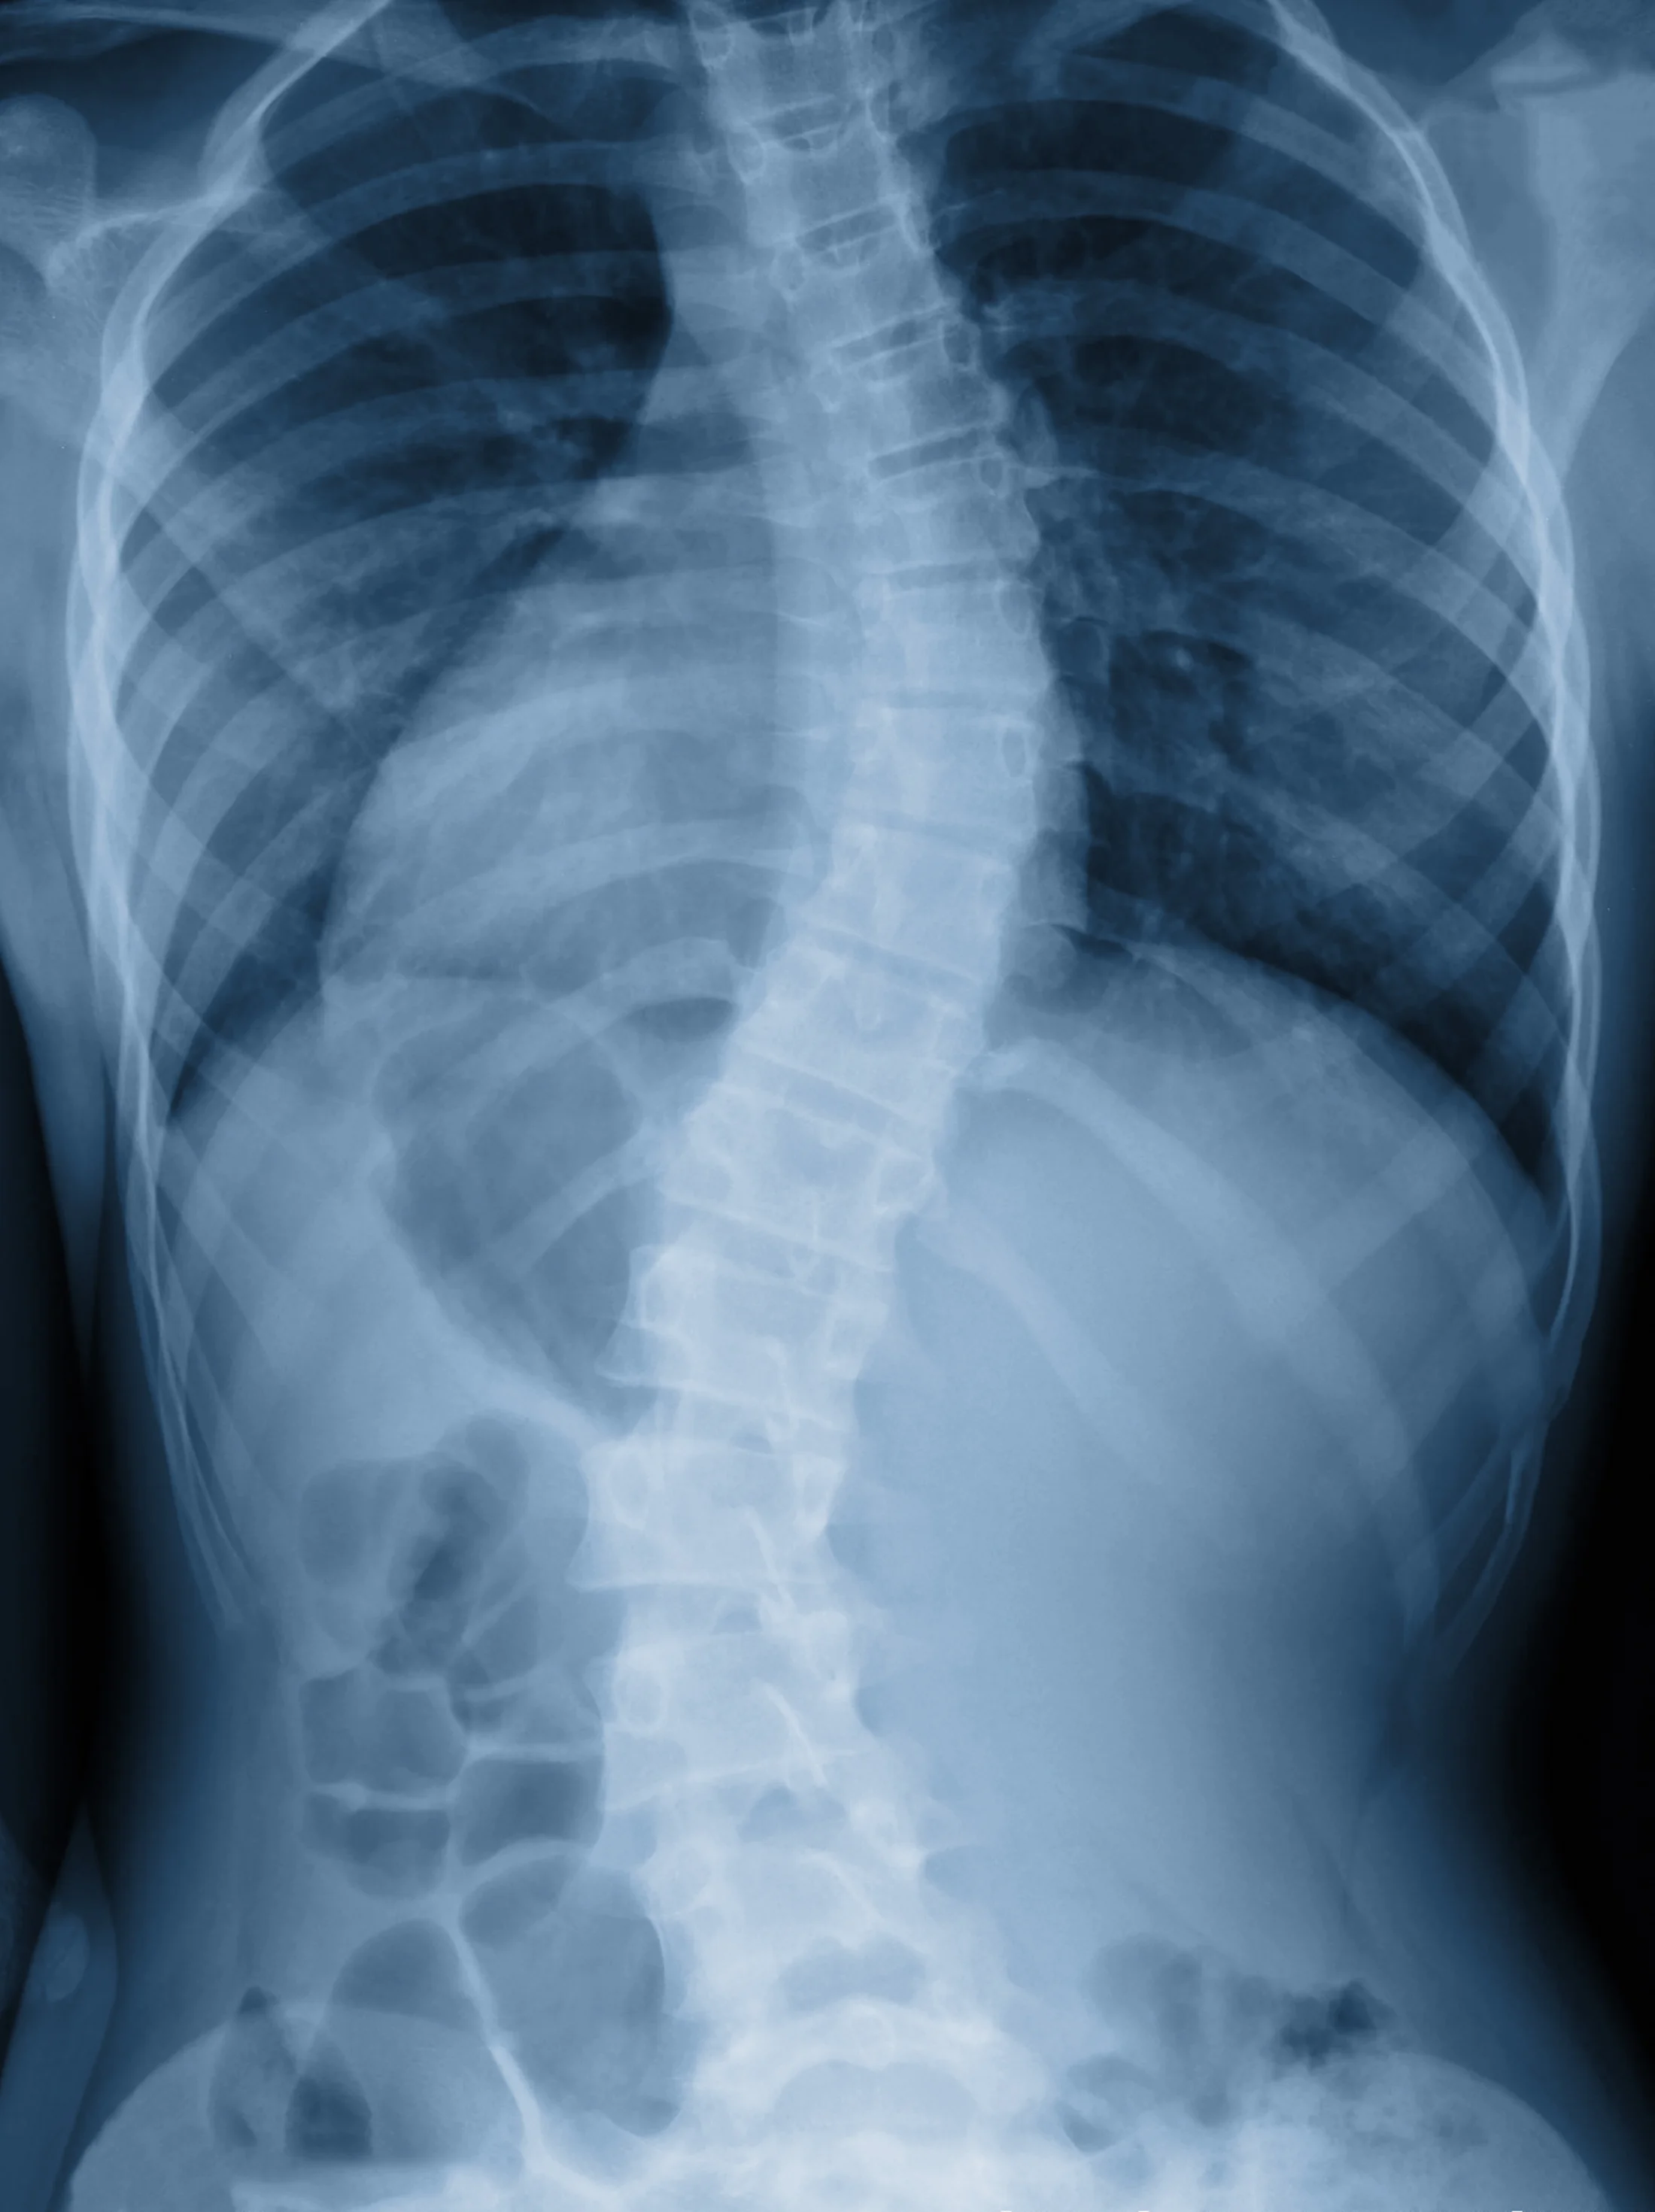

One case might help illustrate the difference between a Feldenkraisian approach and an attempt to have someone conform to an ideal. A woman in her late fifties came to me with a significant scoliosis that was causing her increasing pain and difficulty in her daily activities. She was active, did yoga, acupuncture and pilates, and had always worked to try to minimize the effects of the dramatic twist in her spine in all the ways she could find. Her condition was monitored by doctors and the severity of the irregular curve in her spine was increasing over time, as is the norm with significant scoliosis. She could no longer hike, sit for the length of a theater performance, or do many of her normal daily activities without significant pain. The idea of a spinal fusion, which she had steadfastly avoided for decades, loomed large over her future.

My client with the scoliosis improved a great deal. She was one of the rare people who felt lasting improvements nearly right away, which is largely a testament to how keen her body awareness already was when we started. Then, over time, she became capable of doing things without pain or difficulty that had caused her suffering for years. It is true that after a particularly good lesson the twist in her spine is noticeably reduced, and I think that over time it is reducing more permanently, but her spine will never be straight. Nor should I endeavor to make it so. I have seen x-ray images of her spine and her bones are not symmetrical. If I tried to make her straight, that is, if I tried to have her structure conform to an ideal, I believe I would do her significant harm.